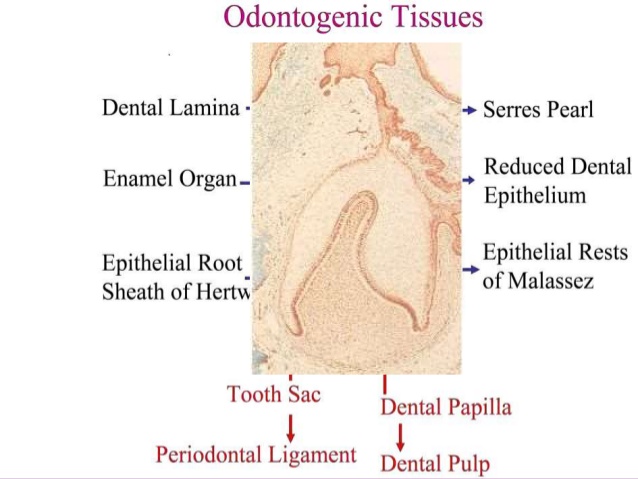

Odontogenic cyst :

The odontogenic cysts are derived from epithelium associated with the development of the dental apparatus . The type of epithelium can vary with most lesions on having stratified squamous but some developmental or fissural cyst in the maxilla may have respiratory epithelium .

• There is general agreement that the odontogenic keratocyst arises from cell rests of the dental lamina.